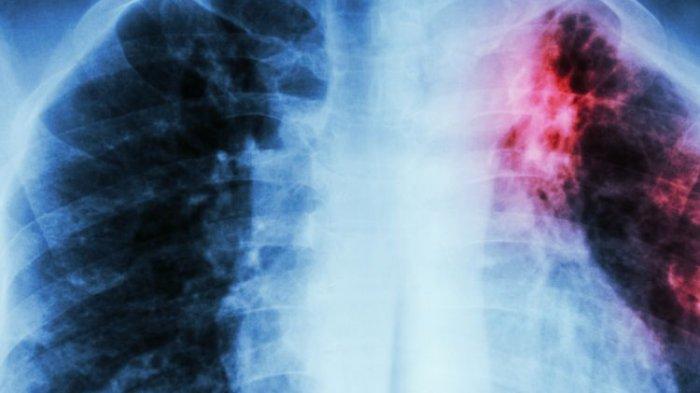

Penyebab dari TBC adalah kuman Mycobacterium tuberculosis, sebetulnya bisa menyerang seluruh organ manusia.

Tapi 70% menyerang paru-paru, karena penyebarannya melalui udara.